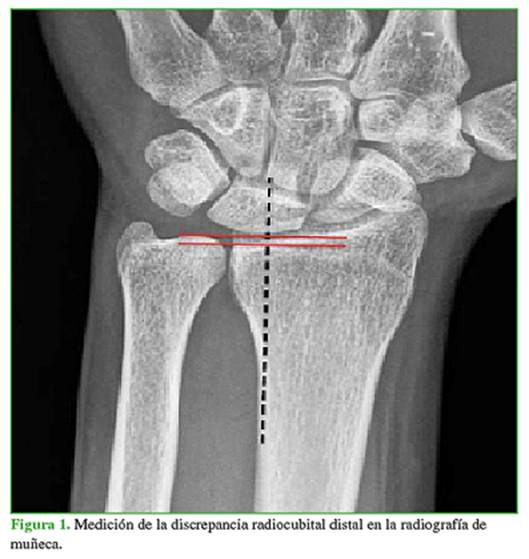

Ante una alta sospecha clínica de ICC, pero sin signos radiográficos, la resonancia magnética es de suma utilidad. En los estadios tempranos, puede observarse fibrilación a nivel del cartílago articular del carpo y de la cabeza del cúbito. El cuadro progresa a edema óseo (Figura 3) y luego a cambios escleróticos.8 En pacientes con signos radiográficos de ICC, la artrorresonancia es útil para evaluar la integridad del FCT y del ligamento lunopiramidal.7,9 El síndrome de ICC debe diferenciarse de otros cuadros que afectan el semilunar. Los cambios radiológicos en la estructura del semilunar son fundamentales para distinguir otras etiologías, como la enfermedad de Kienböck o los quistes intraóseos. En el primer caso, las imágenes son más difusas, afectan la mitad radial del semilunar y no hay compromiso del piramidal ni del domo del cúbito. Los quistes intraóseos aparecen como una imagen de bordes

definidos, sin afectar huesos vecinos.8